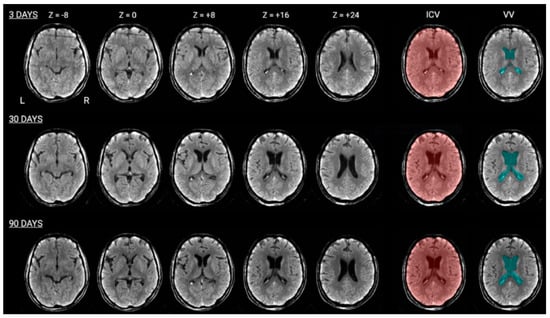

2.2. CT Brain Images

2.4. Brain Damage Evaluation